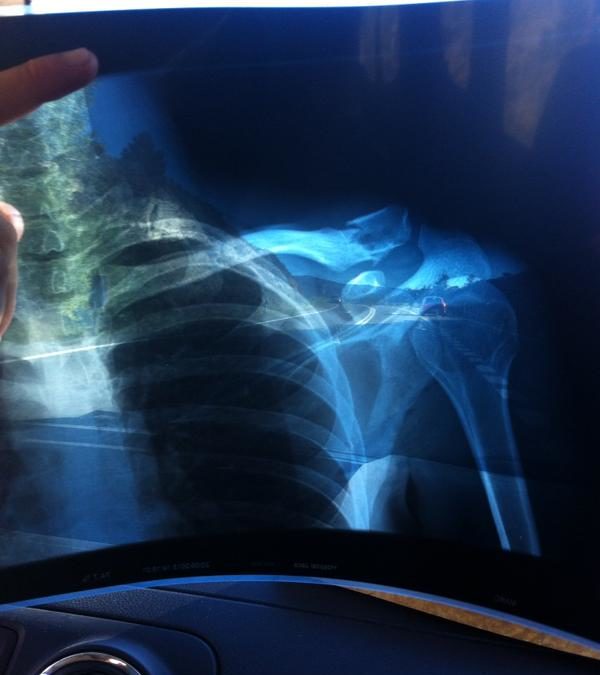

BUESCAS – Marc de Maar heeft zijn voorliefde voor het rijden van mountainbikemarathons moeten bekopen met een sleutelbeenbreuk. De coureur van Roompot, een van de weinige Nederlandse wegrenners die ook regelmatig op de mountainbike koerst, ging afgelopen weekeinde onderuit bij de Quebrantahuesos MTB Marathon in het Spaanse Buescas.

Het is nog onduidelijk hoelang De Maar is uitgeschakeld.